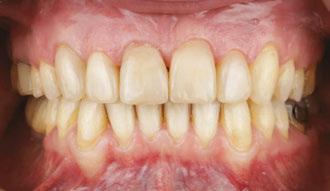

Drs. Claudia Pinter and Stanley Liu illustrate a protocol to improve nasal breathing in orthodontic care 31